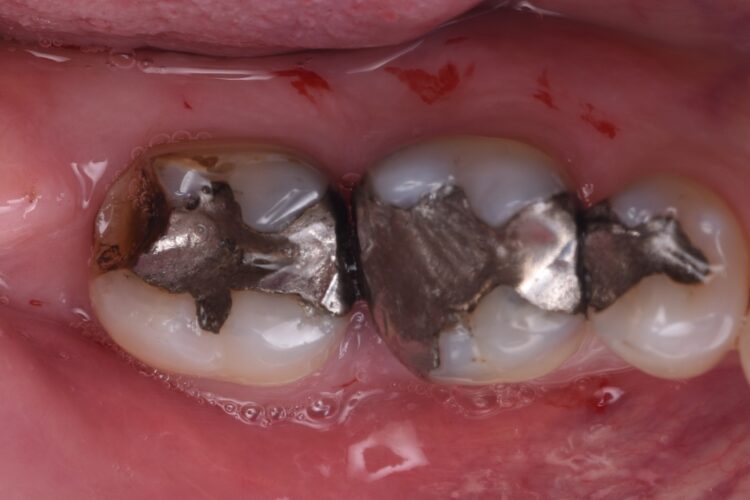

A 57-year-old male patient presented by referral with two failing molars – the LR6 and LR7. The patient had a clear medical history, and both molars exhibited extensive caries and heavy restorations.

Given the absence of acute infection and the availability of adequate bone, we decided on immediate implant placement with delayed loading for both sites. Immediate placement is preferred, as maintaining the existing hard and soft tissue architecture is far more predictable than attempting to rebuild it later.

The failing teeth were sectioned and extracted atraumatically to preserve the surrounding bone. The sockets were thoroughly debrided using Lucas curettes to remove any residual infection or granulation tissue.